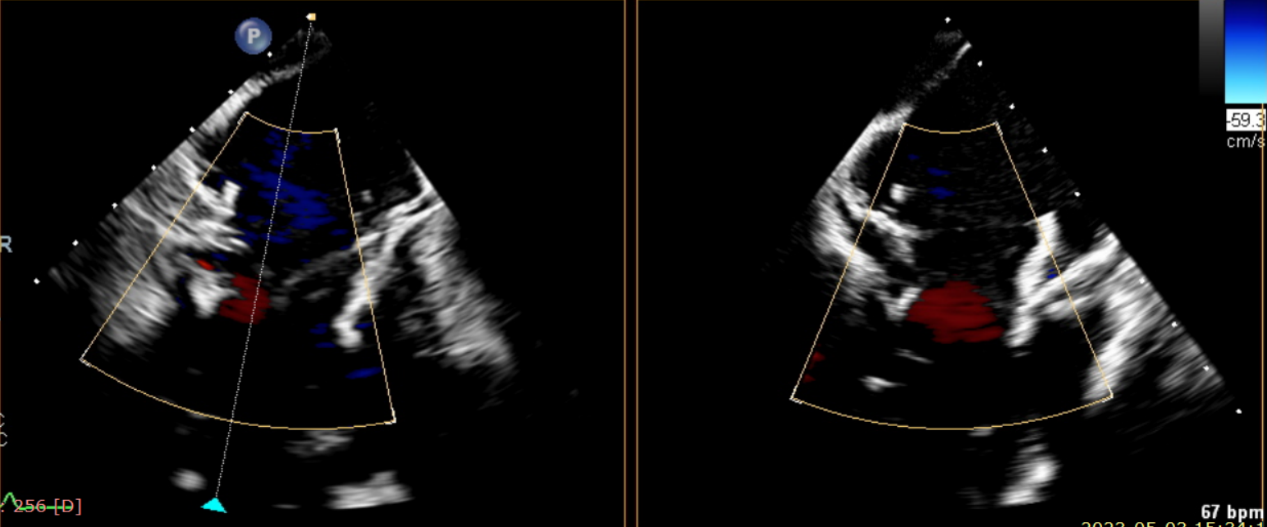

術(shù)前超聲提示大量三尖瓣反流

術(shù)后超聲提示僅殘余輕微瓣周漏